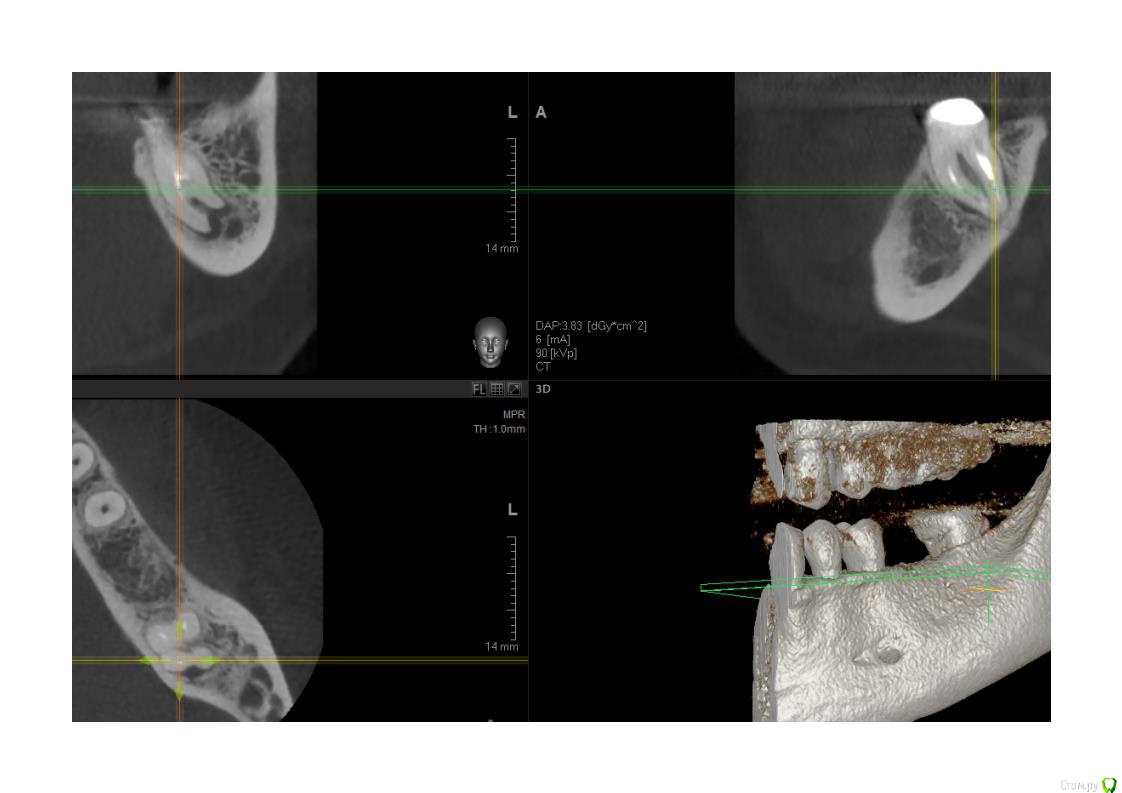

Кукла_Ася Опубликовано 17 октября, 2019 Поделиться Опубликовано 17 октября, 2019 (изменено) Добрый день. Не буду расписывать свою страшную историю с зубами. Со всеми травмами и переломами зубов, а также минимум с 7 гранулемами/кистами за последние 3-4 года. Иначе жалеть начнете))) тем более мне всего 37 лет.Вопрос, задам попроще, чтобы не отнимать ваше драгоценное время. Эту семерку перелечить ведь нельзя? Навылет и имплант?КТ старое, вытащила сама из архива аж от февраля 2018 года. Ибо недавно он поднывал. В мае того же года на 6-ку внизу рядом с нынешнем виновником встал имплантат. Вопрос удаления под вопросом, т.к. на верхней челюсти антагонисты 6 и 7 сейчас проходят эндодонтическое лечение из-за кист на них. Плюс, они похоже только под коронку. Результат непредсказуем, а денег я наскребу только на 1 имплантат в обозримом будущем... и если 6-ку наверху не перелечат, то я правильно понимаю, импланту нижнему нужен будет антагонист... да и жевать чем-то надо.Спасибо, если уделите мне внимание! Изменено 17 октября, 2019 пользователем Кукла_Ася Ссылка на комментарий

DmitrySH Опубликовано 17 октября, 2019 Поделиться Опубликовано 17 октября, 2019 Эту семерку перелечить ведь нельзя? Навылет и имплант? По снимкам ничего особенно ужасного нет, можно и попытаться перелечить. Ссылка на комментарий

krokomot Опубликовано 17 октября, 2019 Поделиться Опубликовано 17 октября, 2019 Похоже на перелом по фуркации(место расхождения корней), но это не точно, можно еще прицельный сделать и тщательная ревизия под увеличением, в случае отсуствия трещины шансы есть, но только у профи!..., а это по стоимости полимплантата Ссылка на комментарий